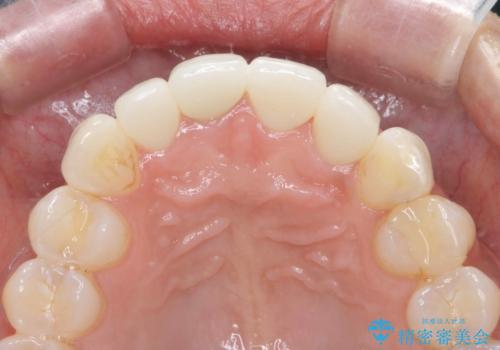

金属色の見える前歯 オールセラミックで審美治療

- 前歯のクラウンの見た目が不自然、歯の根元が見えたり金属色が気になるので改善したい、とセラミック治療を希望され来院されました。

歯肉の位置変化による審美障害を改善するため、オールセラミックジルコニアクラウンで再治療を行い審美性の改善を計画します。

見た目が自然になり、色調も天然の歯とおなじような透明感のある色調が再現され、大変喜んでいただくことができました。